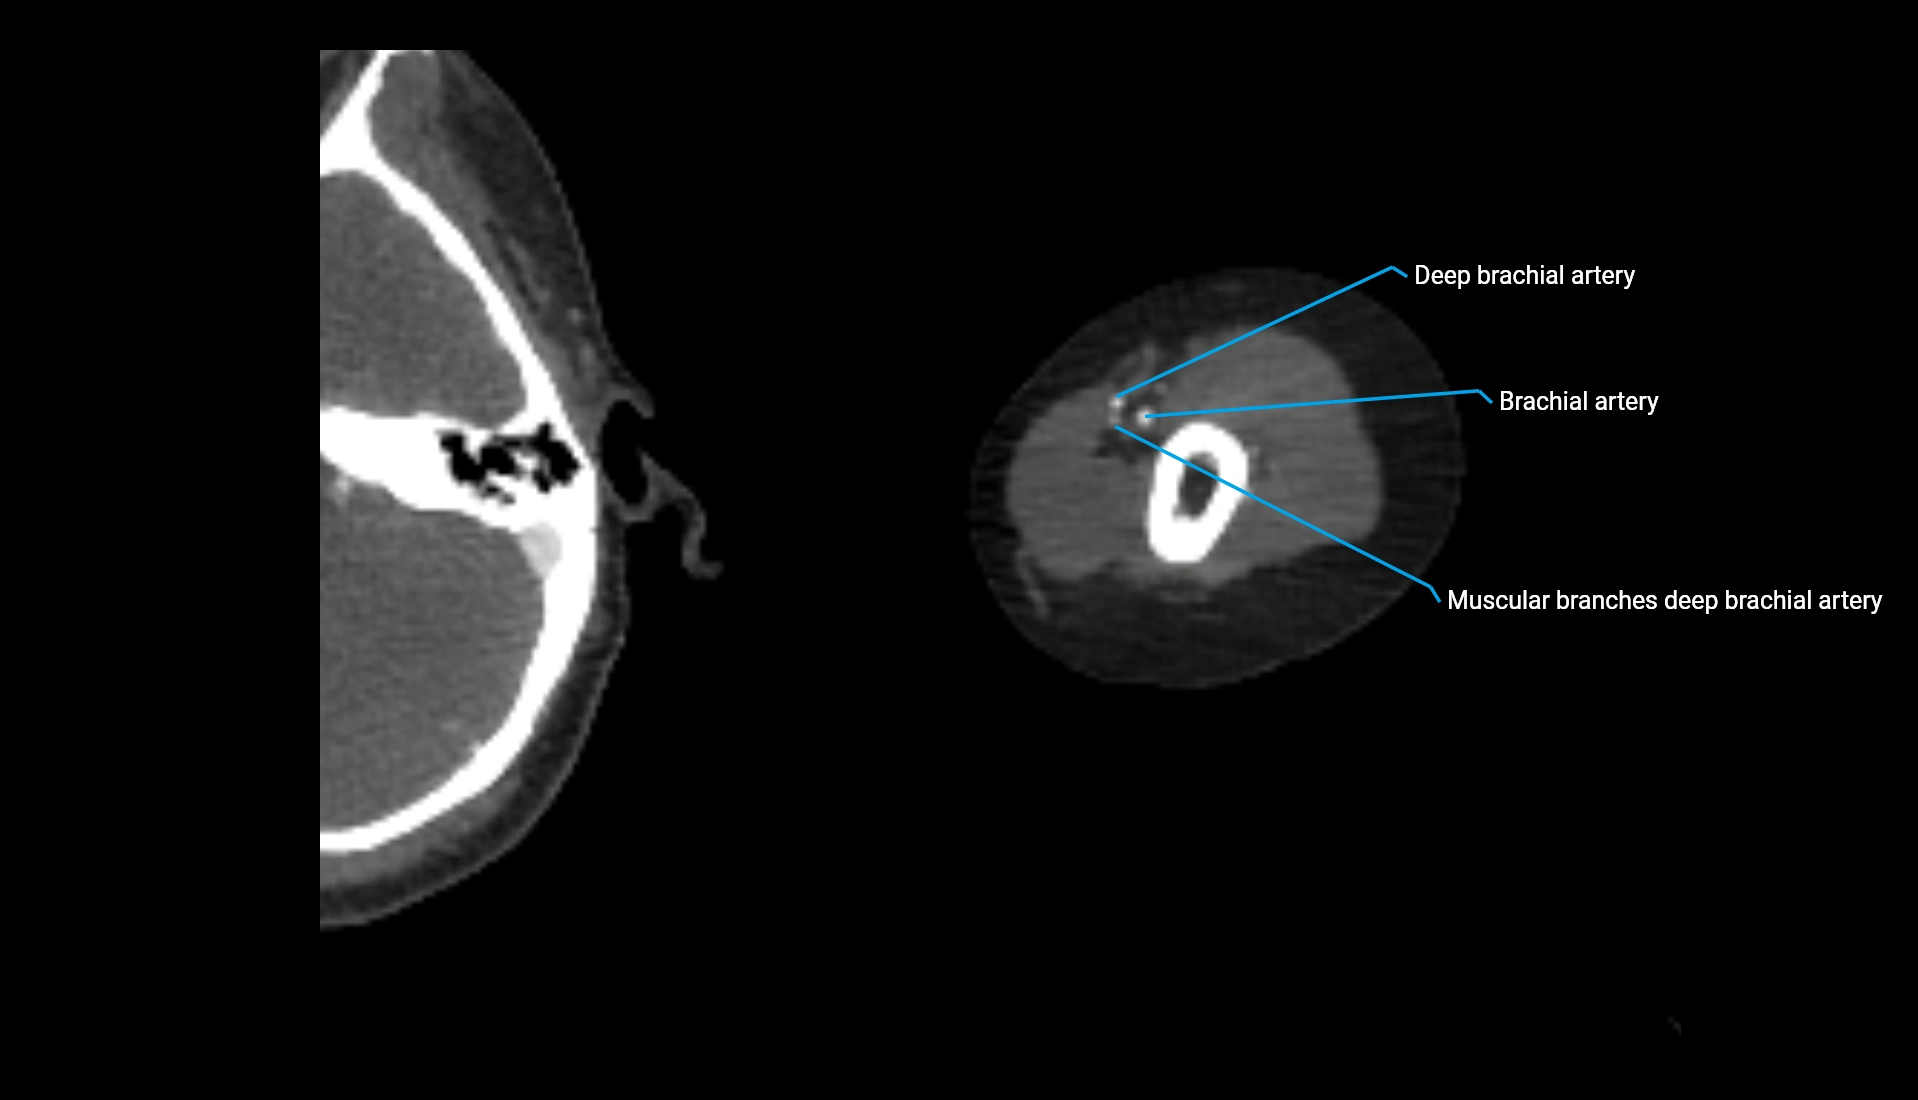

CT Appearance

Non-Contrast CT:

• Cortex: High-density, sharply defined

• Subchondral bone: Dense cancellous matrix

• Articular surface: Smooth concave contour articulating with the capitellum

• Excellent for evaluating bone integrity, alignment, and subtle fractures